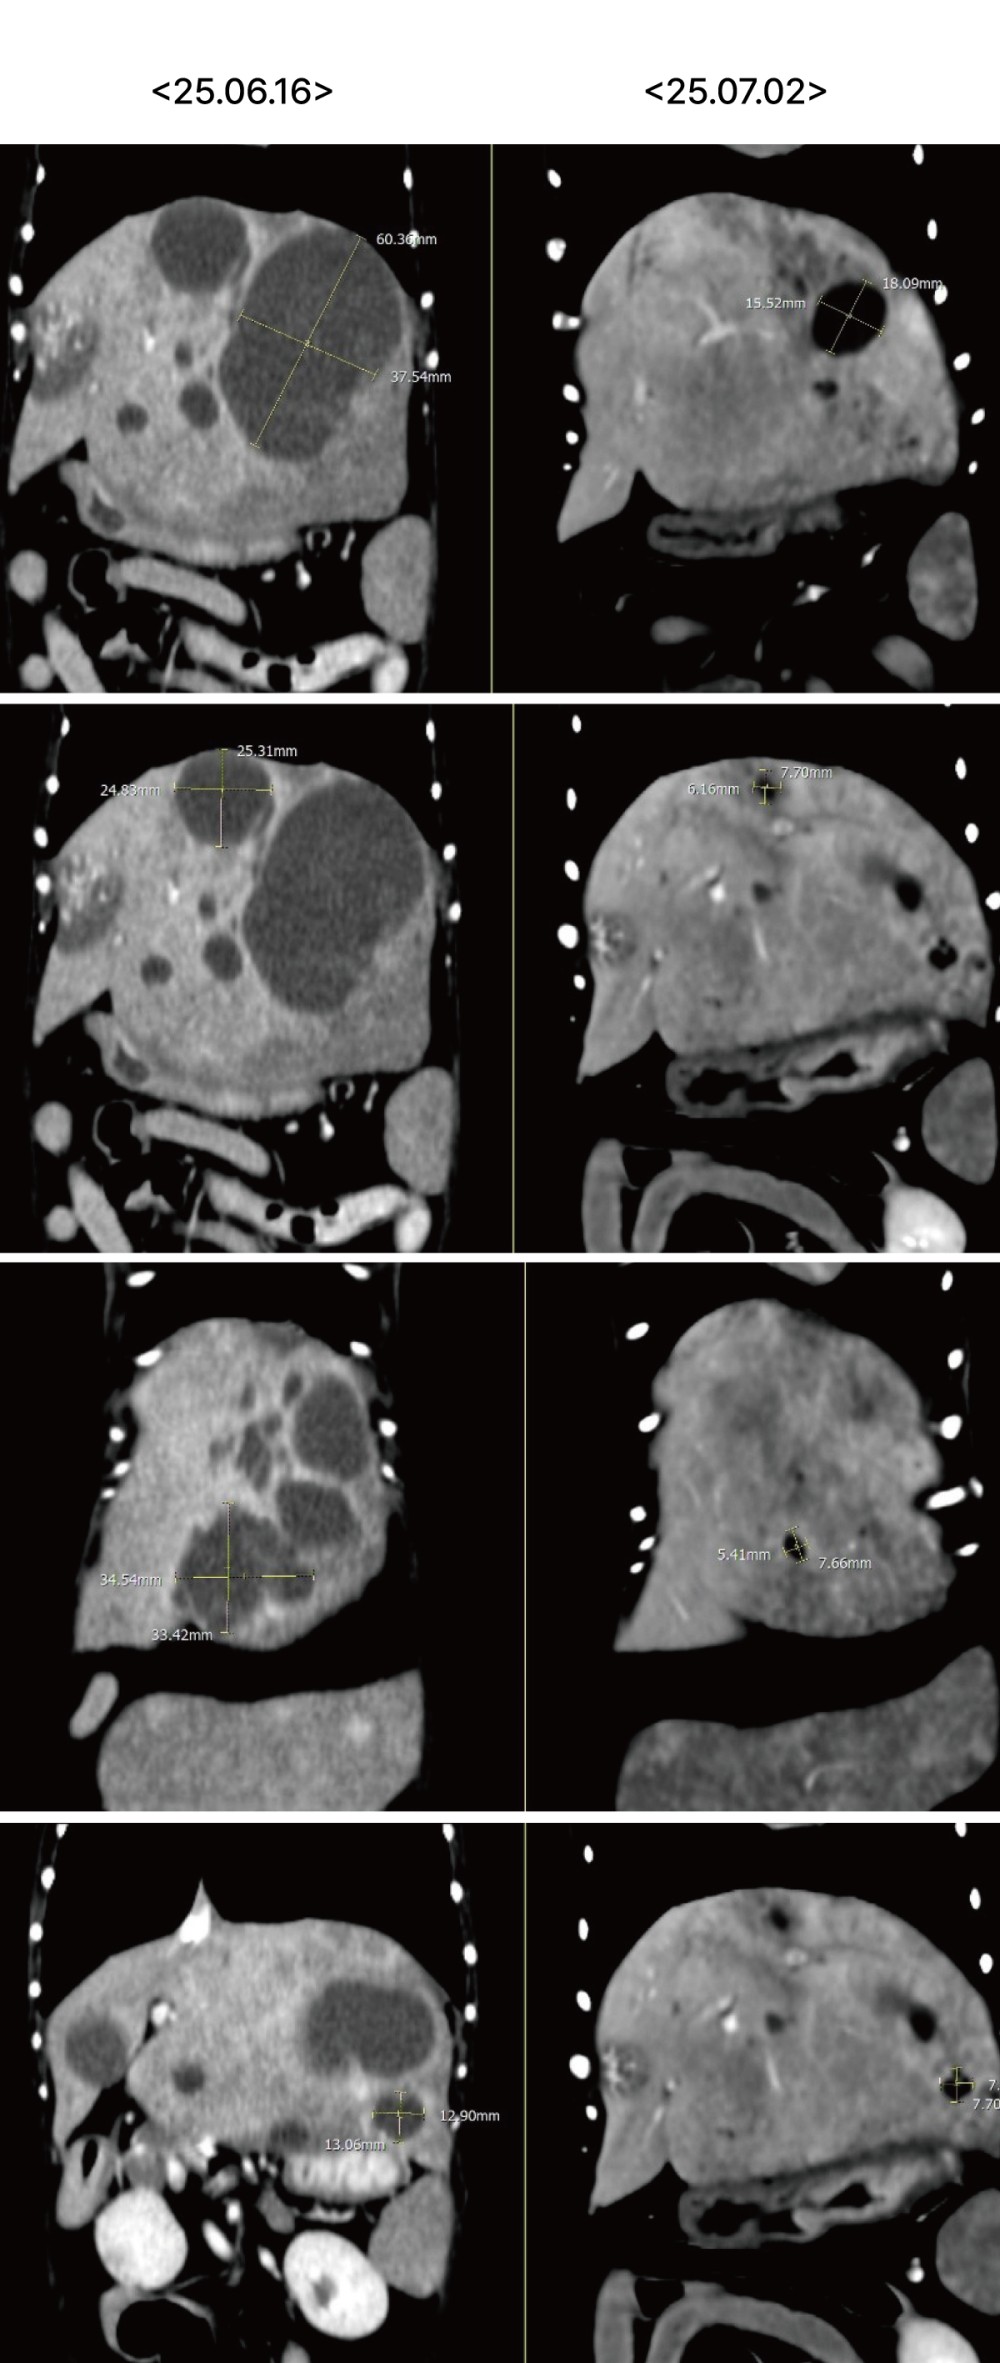

실제로 추적 CT에서도 간 내 낭성 병변의 크기가 뚜렷하게 감소하고 림프절 크기 또한 감소하여 처치에 대한 반응이 명확하게 확인되었습니다 .

45dea41c691aea1975c51c7a51847d38_1775038428_7096.jpg

▲ 좌측 내측엽과 가측엽에 위치하던 cystic lesion의 크기 뚜렷한 감소 및 불규칙한 변연으로 변화

45dea41c691aea1975c51c7a51847d38_1775038454_7347.jpg

▲ 이전 검사에서 뚜렷하게 종대되어 관찰되었던 간 림프절 크기 감소

45dea41c691aea1975c51c7a51847d38_1775038470_0844.jpg

▲ 대동맥 림프절의 크기 감소​